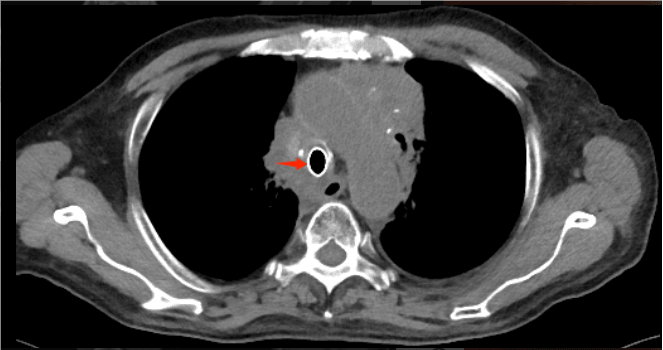

72岁的程爷爷,因“确诊肺癌5年余,咳嗽、咳痰伴间断咯血两个月”入院。检查发现其左肺鳞癌已进展至Ⅳ期,肿瘤侵犯导致气管中下段及隆突区域形成约4.5厘米的极重度狭窄,严重影响呼吸功能,同时患者合并心房颤动、心包积液等多系统并发症,治疗难度极高。

术前胸部CT见患者气道狭窄,呈一缝隙